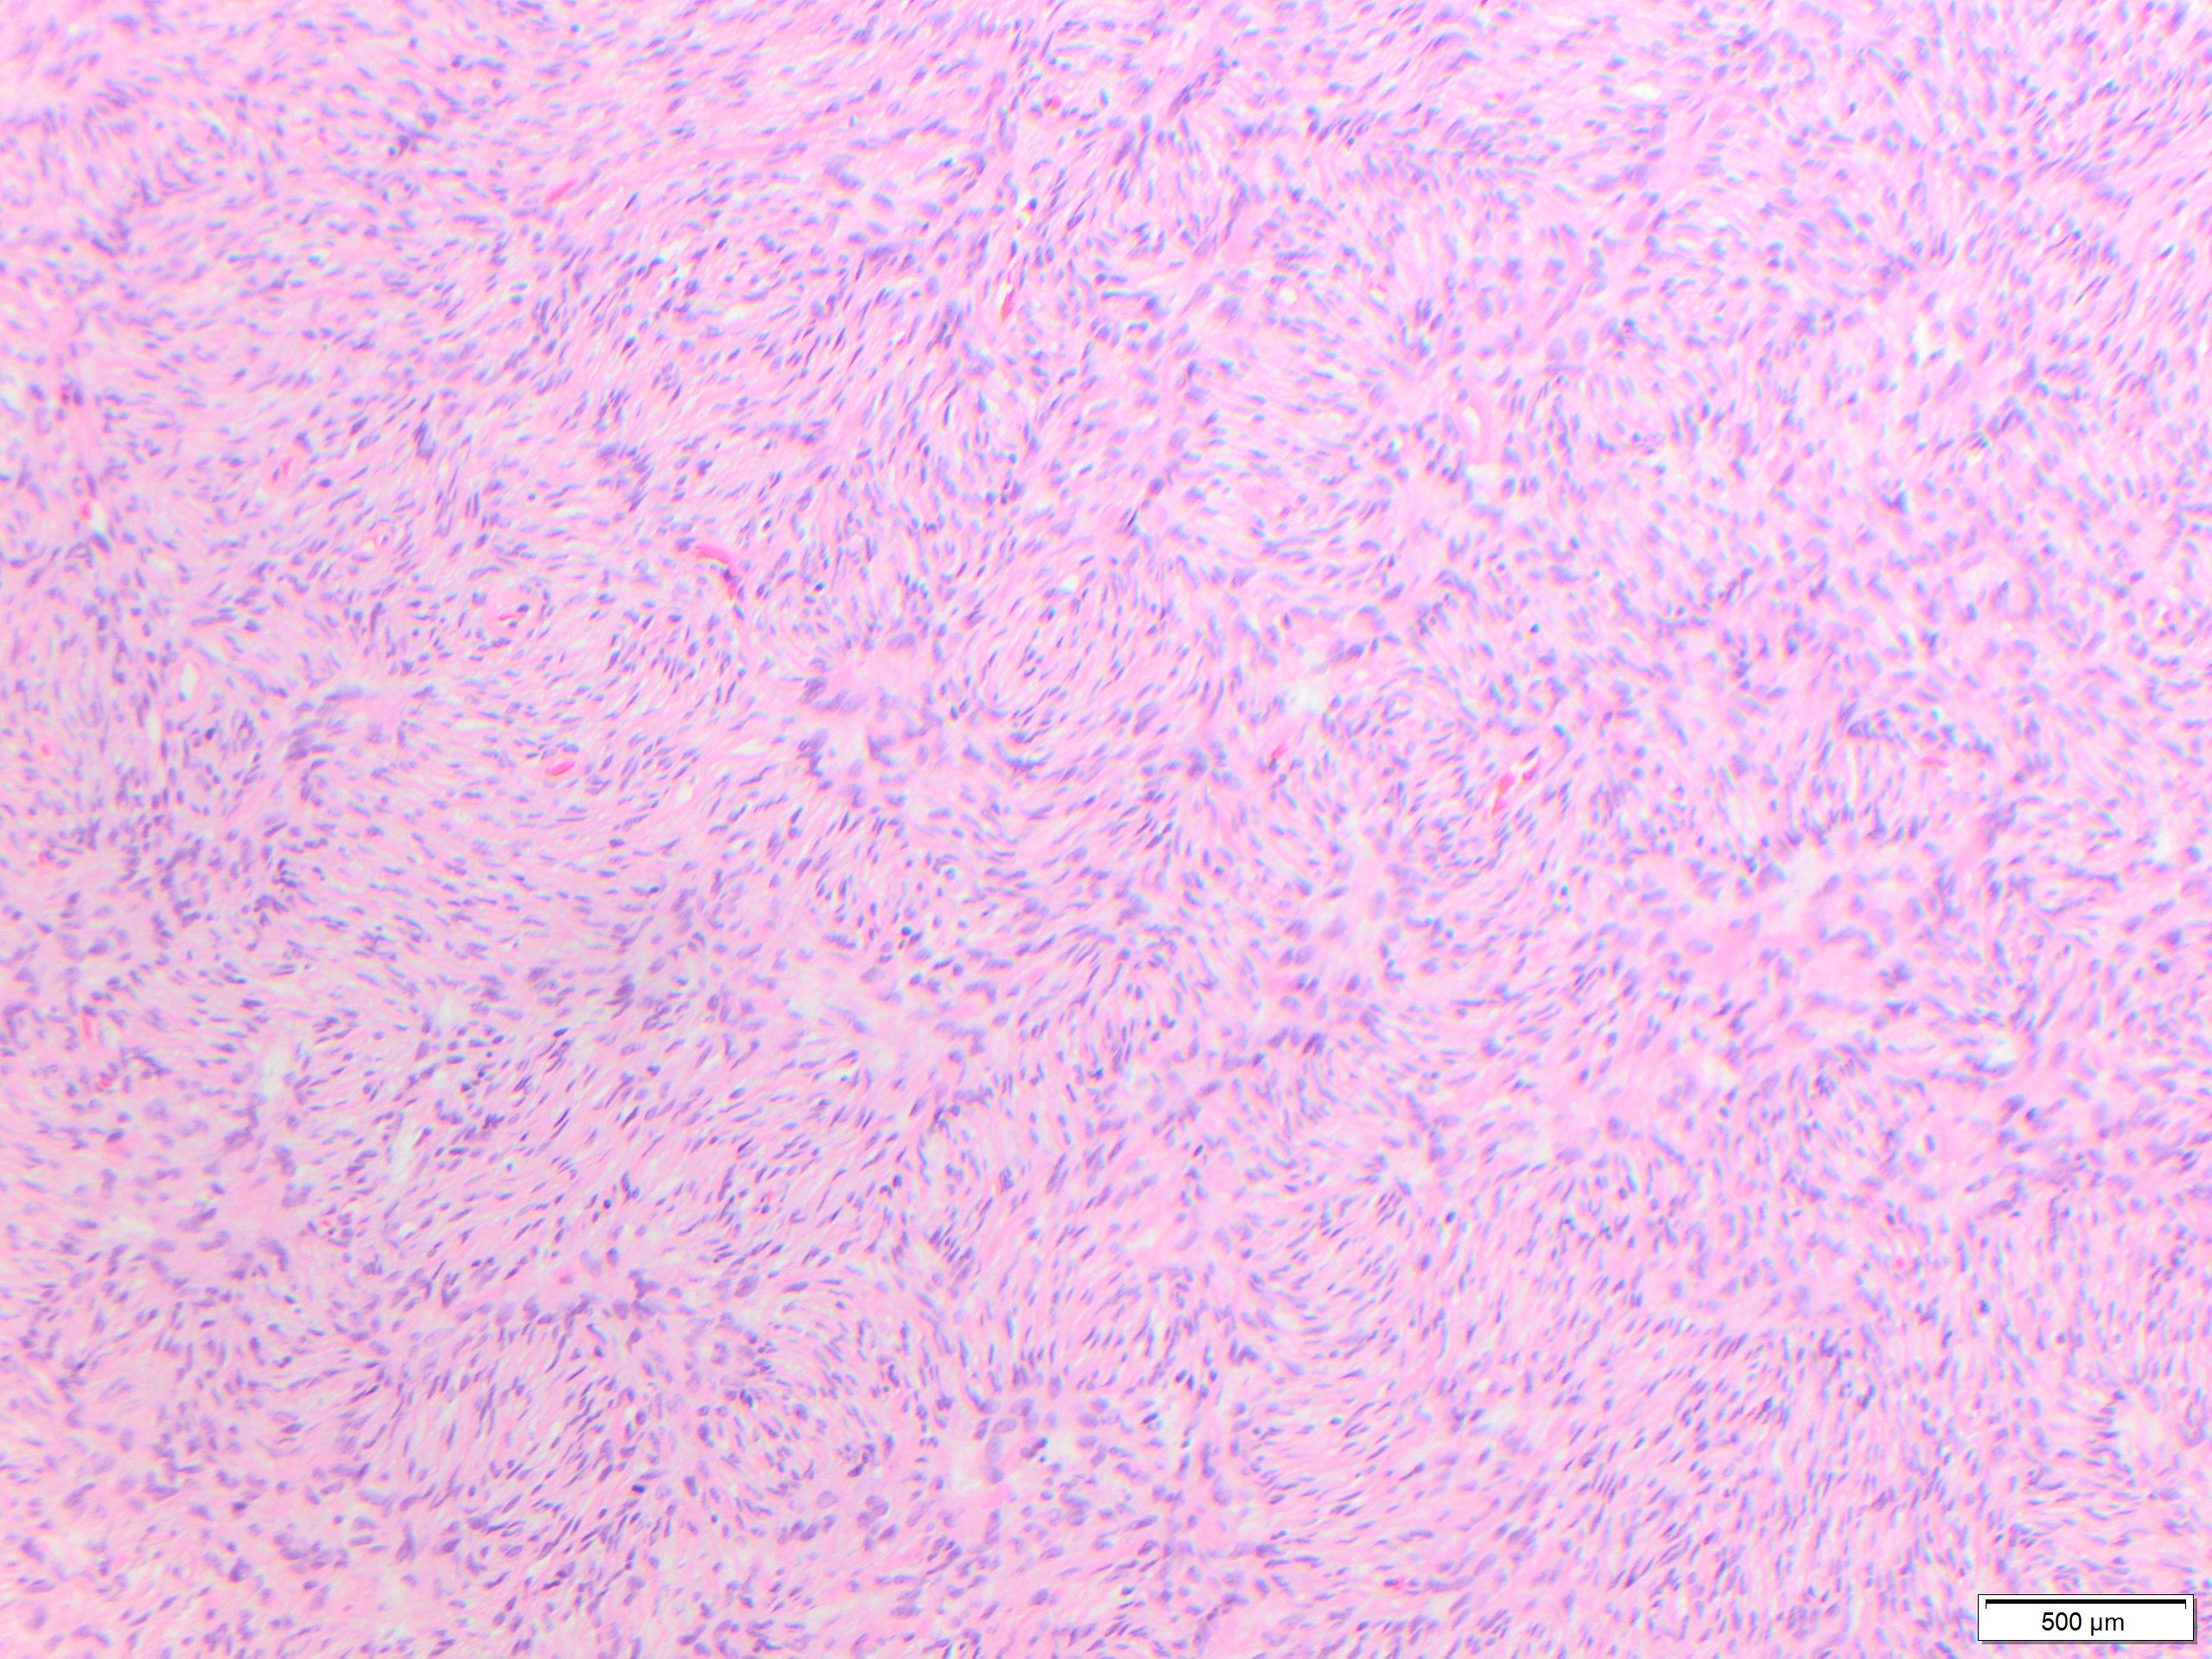

While these tumors may appear grossly circumscribed, microscopically DFSP are ill-defined with diffuse infiltration of dermis and subcutis. The tumor is composed of uniform spindled cells with collagenous stroma, often arranged in a storiform or “cartwheel” pattern, with infiltration of fat lobules and adnexal structures at the periphery. Some DFSP lack the collagenous storiform arrangement and instead display variably myxoid stroma, and some DFSP, like this example, may display myoid differentiation and so called “myoid-bodies” which may also be seen in other types of mesenchymal tumors. By immunohistochemistry DFSP are diffusely positive for CD34, and negative for S100, smooth muscle actin (SMA) and desmin, except myoid areas when present, are positive for SMA. Areas with herringbone architecture and loss of CD34 staining, may indicate fibrosarcomatous transformation. The histologic differential diagnosis of DFSP includes benign fibrous histiocytoma, neurofibroma, plaque-like CD34-positive dermal fibroma, and superficial acral fibromyxoma.